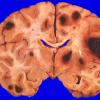

NEOPLASMS (METASTASES)

Melanoma (7)